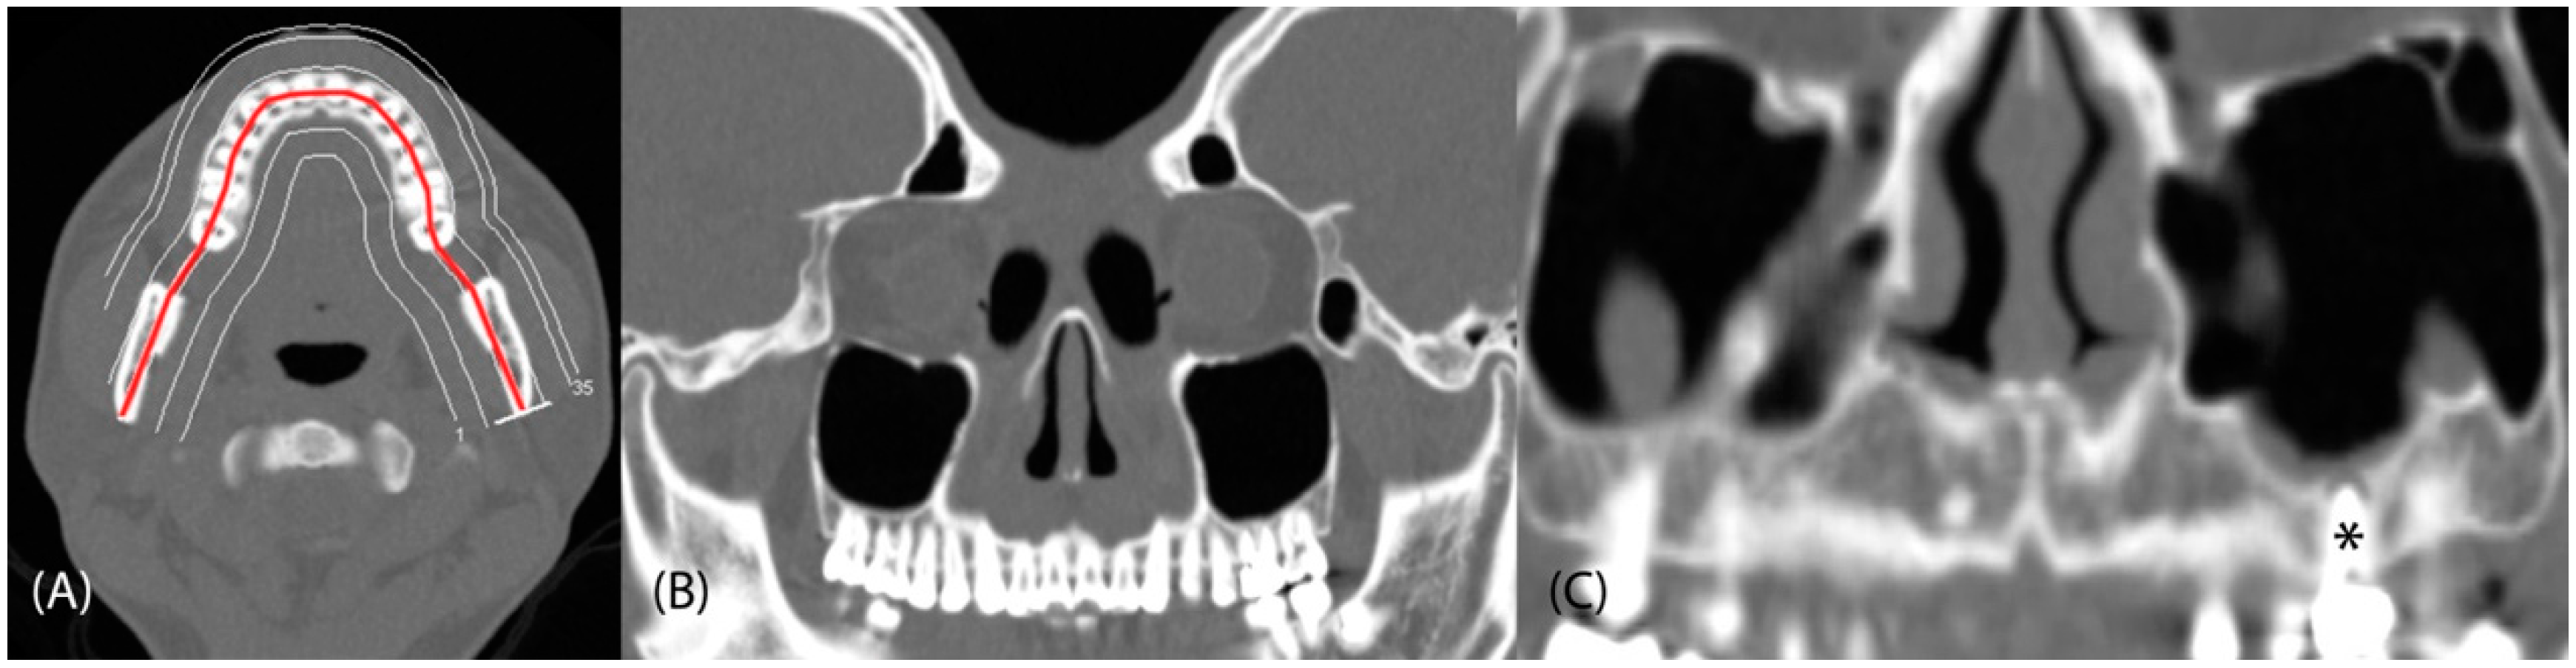

1. Introduction

2. Materials and Methods

2.2. Assessment of Dental Pathologies and Sinus Conditions